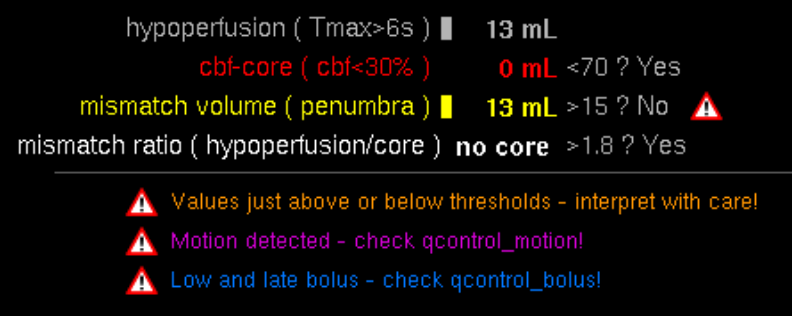

Des Weiteren ist mRay in der Lage eine Verarbeitung von Bildern durchzuführen und so Veränderungen bzw. Anomalien in Geweben zu finden, zu visualisieren und zu quantifizieren. Das Bildverarbeitungsmodul mRay VEOcore kann verwendet werden, um Bilder des Gehirns von Bildgebungsmodalitäten wie CT, Perfusions-CT oder MRT mit diffusionsgewichteter Auswertung (DWI) zu prozessieren. Als Ergebnis werden Kontrastveränderungen über die Zeit als farbige Perfusionskarten angezeigt, dies beinhaltet auch flussbasierte Parameter und Gewebeblutvolumen Berechnungen.

Die Perfusionsanalyse von Aufnahmen des Gehirns ermöglicht die Darstellung und Quantifizierung von minderdurchblutetem Gewebe (Penumbra), nicht-durchblutetem Gewebe (Kerngewebe) und dem Mismatch-Ratio zwischen den beiden Werten. Die berechneten Werte können der Unterstützung bei einer Entscheidungsfindung dienen, die auf der Beurteilung des Ausmaßes der Schädigung von Geweben basiert.